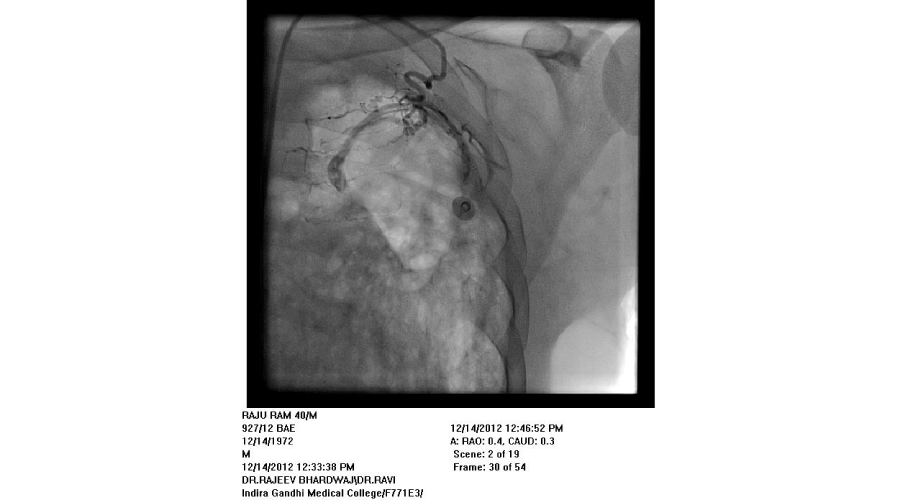

Patients admitted with moderate to severe hemoptysis in pulmonary medicine or general medicine department were the subjects of study. The patients were subjected to routine blood examination, X ray of chest, and CT scan of chest (Except in emergent situation). If required, bronchoscopy was done to localize the side of bleeding and for diagnostic purposes. Informed consent was taken from all patients. Commonest approach was from right femoral artery puncture. Seven French sheath was inserted in the femoral artery with the help of Seldienger technique. According to the protocol, bronchial arteries, intercostal arteries, subclavial arteries and its branches including the internal mammary arteries were selectively hooked with a catheter and contrast was injected into these arteries to see for the signs of bleeding. Initial attempt was made to see for bleeding source on the side suggested by X-ray or CT scan or bronchoscopy. Before the completion of procedure, vessels of other side were screened. If no bleeding vessel was found after screening on both sides, pulmonary arteriography was done with pig tail catheter to see for the source of bleeding from pulmonary artery. An artery was considered abnormal/ potential bleeder, if extravasation of contrast, aneurysm, increased caliber with tortuosity, vascular tufts, arterio-arterial or arterio-venous fistulas were seen. Once diseased artery was identified, it was selectively cannulated with a catheter. Most commonly used catheters were right Judikin, Cobra I, and Simmon I. The vessels were hooked deeply with the catheter, with the support of .018 inch guide wire. The vessel was then embolized with poly vinyl alcohol (PVA) particles mixed with contrast agent. The particles were injected till vessel was occluded or reflux of contrast was seen. If a vessel could not be hooked deeply, a micro-catheter was passed through the catheter and PVA particles were injected through micro-catheter. Size of particles used was 500-700 microns. If it was difficult to cannulate the branches of subclavian artery selectively, due to fibrosis, the artery was approached from radial artery puncture. Criteria used for successful embolization was that all diseased arteries were embolized. If spinal artery was seen on cannulation of a bronchial artery, the embolization was done distal to its origin to avoid inadvertent embolization of spinal artery.

We found that most of the cases required embolization of multiple vessels. In around half of the patients, both bronchial and systemic vessels required embolization. In around one fourth of patients, only bronchial and in another one fourth, only systemic vessels were the source of bleeding. In contrast to other studies, out of 192 vessels embolized, around 37% vessels were arising from subclavian arteries, (including 10% internal mammary arteries) and in 27% intercoastal arteries were the source of bleeding. Swansen et al., embolized the following arteries: right bronchial artery (34), left bronchial artery (11); combined right and left bronchial trunk (9); intercostal arteries (45); right internal mammary artery (8); left internal mammary artery (8); inferior phrenic artery (10); lateral thoracic arteries (3); thyrocervical trunk (2); and a left gastric artery (1) [11]. The complications of BAE in this study included subintimal dissection in two patients (4%), arterial perforation by a guide wire in one patient (2%), and reflux of embolic material into the aorta without adverse sequelae in one patient (2%). Pleuritic chest pain post procedure occurred in two patients (4%), shoulder pain post procedure in one patient (2%), and transient dysphagia in one patient (2%). One patient developed a groin hematoma at the puncture site.(Figures 1-5)